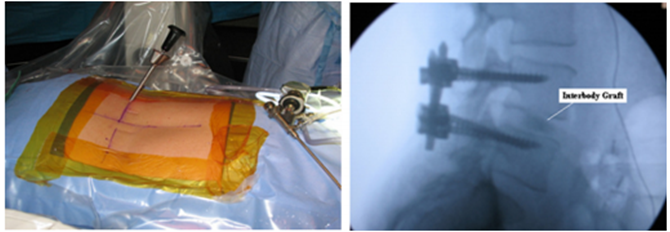

2015年,Morgenstern 报道了改良pTLIF手术治疗椎间盘退行性疾病合并腰椎滑脱(II度以内)的效果。该研究采用了新型的可撑开O型融合器。对比peek椎间融合器以及同型号可撑开的金属O型融合器的治疗效果及融合率,两组之间并没有明显的差异。如图可见,在pTLIF的基础上加用了后路经皮椎弓根固定。平均随访时间为37月,患者ODI/VAS均有明显的改善,该技术对于椎间盘退行性疾病合并腰椎滑脱(II度以内)获得了比较好的治疗及复位效果。

为了避免对出口神经根的损伤,一些学者开始尝试改良工作通道的建立方法。2018年周跃教授团队在Said等基础上改良了工作通道的建立方法,其工作通道的建立同TESSYS技术,减压范围较EndoLIF的范围更加广泛,将此技术命名为PELIF(Percutaneous Endoscopic Lumbar Interbody Fusion,PELIF);长时间随访结果显示所有患者椎间都完成了骨性融合,生活质量较以前得到很大程度提高。

为了更好地监视内镜下减压及融合过程,减少并发症的发生。2017年Youn等报道了全内镜下腰椎减压融合技术(Full endoscopic lumbar interbody fusion ,FELIF),该技术与之前技术相比,优势在于铰刀和Cage置入椎间隙的过程也在内镜监视下进行,从而可以有效避免相关神经损伤和融合器位置不佳的问题。